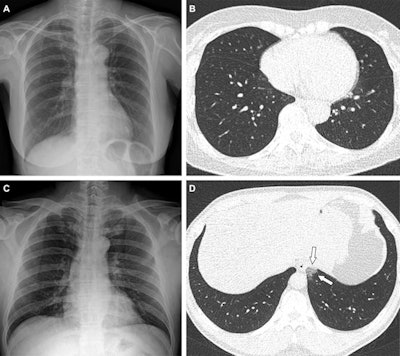

"[We found that] patients with COVID-19 breakthrough infections had a higher proportion of CT scans without pneumonia compared to unvaccinated patients, and vaccination status was significantly associated with the need for supplemental oxygen and [intensive care unit (ICU)] admission," the group wrote.

The investigators found a dramatic difference in the incidence of breakthrough COVID-19 infection by vaccination status, as well as the percentage of negative results on chest CT (of the total patient cohort, 54% underwent chest CT while in the hospital). Lee and colleagues also found that fully vaccinated patients also had lower risk of needing supplemental oxygen and ICU admission than unvaccinated people.

Negative results for COVID-19 pneumonia on CT | 22% | 30% | 59% |